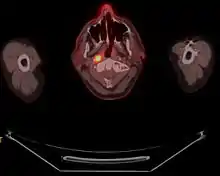

یک اسکن کامل از بدن، که معمولاً از میانه ران تا به بالای سر است، ۵ تا ۴۰ دقیقه، وابسته به پروتکلهای تصویربرداری و تکنولوژی تجهیزات به کار رفته، طول میکشد. تومورهای با متابولیسم بالا به صورت پیکسل یا وکسلهایی که به صورت رنگهای ساختگی کد میشوند بر روی تصاویر CT کد شده به صورت خاکستری نشان داده میشوند. مقادیر جذب استاندارد توسط نرمافزار برای هر ناحیه با متابولیسم بالا در تصویر شناسایی شده، محاسبه میشود. با وجود اینکه تصوربرداری کارکردی تخمین کالبدشناسی دقیقی از محدوده آن مشخص نمیکند، این عمل یک کمی سازی برای اندازه تومور ایجاد میکند. دز FDG مورد نیاز برای انجام ۵-۴ آزمایش بهطور روزانه در دو یا چند نوبت در روز، توسط سازندههای این مواد به محل تصویربرداری میرسد.